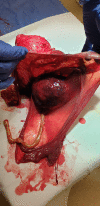

Case presentation: We present a case of 43-year-old tercigravida with a history of previous laparotomic myomectomy and subsequent cesarean section. The subsequent pregnancy was complicated by uterine wall loosening and rupture at the site of the previous uterine scar after myomectomy and complete fetal expulsion into the abdominal cavity. The diagnosis was made at 24 + 6 weeks of gestation. Considering the absence of clinical symptomatology and the good condition of the fetus, a conservative approach was chosen with intensive monitoring of the maternal and fetal conditions. The pregnancy ended by elective cesarean section and hysterectomy at 28 + 0 weeks of gestation. The postpartum course was uneventful and the newborn was discharged to home care 63 days after delivery.